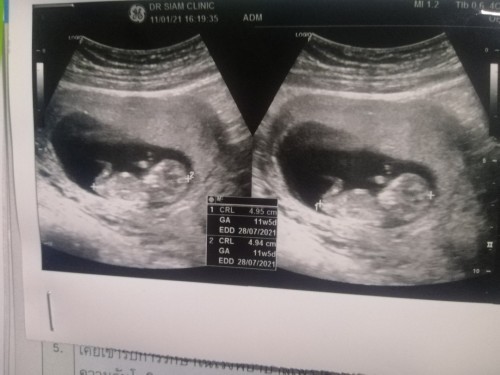

12Wค่ะ

3เดือนแล้วค่ะ..เริ่มเห็นแขน ขา บ้านใหนเหมือนกันมั๊ยค่ะ???3เดือนเห็นชัดขนาดนี้เหมือนกันรึป่าวค่ะ

11w ค่ะเห็นชัดเหมือนกันดุ๊กดิ๊กๆเก่งอีกต่างหาก

ของเราซาวด์ตอน 11 week 5 day ก็ชัดมากเลยจ้า ☺️